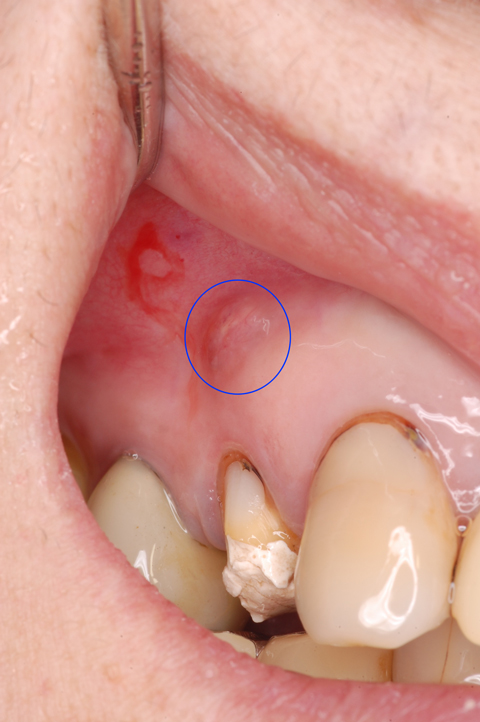

この歯です。青丸の中がサイナストラクト(フィステル)。歯根破折の場合、サイナストラクトは比較的歯冠寄りに出現します。なお出血している部分は麻酔注射によるものです。